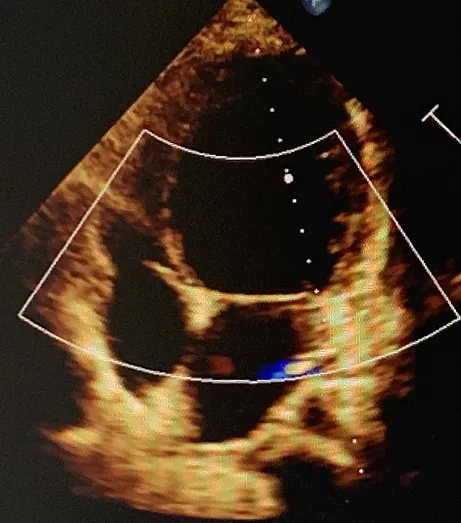

其病理特征为心室内存在异常粗大的肌小梁和交错的深隐窝,左室心肌存在致密化和非致密化两层,以心尖部和左室游离壁中部*为多见。

① 典型的两层不同 的心肌结构,外层即致密化层较薄,内层即非致密化层较厚,肌小梁之间可见深陷隐窝。

超声心动图诊断标准为心室收缩末期非致密化层与致密化层比值 >2(图7),幼儿为>1.4 ;

图 7 病变累及节段心内膜面非致密心肌层增厚,回声增强,近心外膜面致密心

肌变薄,比值约 3:1